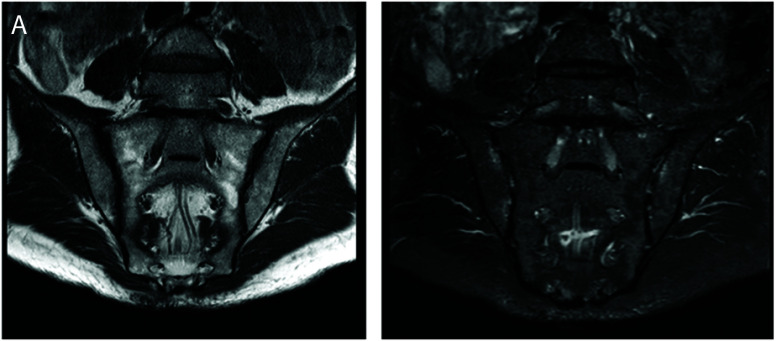

Abstract Image